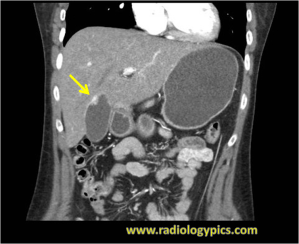

History: 50 year old female with melanoma.

Gallbladder Metastases of Melanoma - Coronal CT of the abdomen with contrast reveals an enhancing soft tissue nodule along the wall of the gallbladder compatible with melanoma metastases.

This is a case of metastatic malignant melanoma to the gallbladder. Melanoma is the most common cancer to metastasize to the gallbladder, and it usually occurs in the setting of widespread metastatic disease. Melanoma metastases are usually hyperenhancing. The differential diagnosis in this case would include other causes of gallbladder wall thickening. These include benign gallbladder polyps, adenomyomatosis, polypoid gallbladder carcinoma, and possibly tumefactive sludge.

Treatment for solitary gallbladder metastasis of melanoma is surgical excision; however, these patients have a poor prognosis.